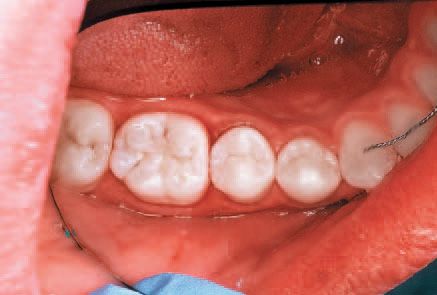

Research supports the use of the system on interproximal lesions from E1-D1, and recently the American Dental Association announced that resin infiltration of incipient smooth surface lesions is now covered by a 2013 CDT Code classification (D2990) to allow for accurate coding and billing for this new technology.16 A 20-year-old male presented for routine dental care, including prophylaxis, oral exam and radiographs.

An interproximal lesion was noted on the bitewing on the distal proximal surface of tooth No. 29 (Figs. 3 and 4). The patient was informed of the diagnosis and his options for treatment, which ranged from monitoring the lesion over time to prepping and restoring in a traditional method. We also discussed with him a new technology that fills, reinforces and stabilizes demineralized enamel without removing healthy tooth structure and arrests the progress of the proximal lesion. The patient eagerly opted for the ICON infiltration concept.

No local anesthesia is necessary, but rubber dam isolation is recommended to assist in the success of the ICON resin infiltration procedure. Cleanse the isolated tooth with NaOCl or Consepsis and rinse thoroughly with a water spray and air dry. The teeth are separated using one of the enclosed plastic wedges, which will allow for the placement of the Proximal-Tip foil matrix delivery system. The wedge can be maintained interproximally during the entire procedure if necessary (Fig. 5).